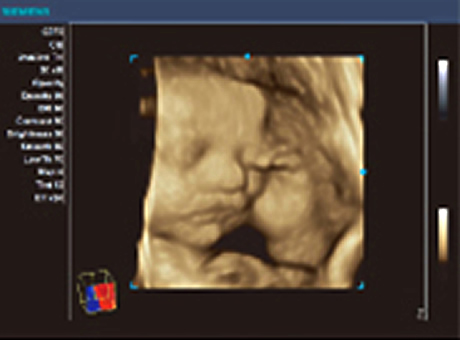

| 超音波検査 | 当院では検診の際、必ず超音波検査を行っております。 当院は最新鋭の4D超音波診断装置【ACUSON X700】を導入しています。 通常は2D超音波検査ですが、ご希望により4D超音波も行っています。 ※超音波の映像をDVDに録画します。赤ちゃんの成長記録の記念にしてください。 (DVDは当院で用意しております。録画は無料です。) ※超音波の映像を一緒に見られるモニターがありますので、ご主人やお子様とぜひ一緒にご来院ください。 |

| 4D超音波とは… | 4D超音波は赤ちゃんの様子をリアルタイムで観察できます。 ■4D超音波 - 立体画像を動画として見ることが出来ます ■3D超音波 - 立体静止画像です ■2D超音波 - 通常の検診時に見ている平面画像です |

赤ちゃんの様子をリアルタイムで観察し、DVDに録画いたします。 対象は妊娠20週~30週の方(24週~28週が最適)です。 ![]() ![]() ![]() 赤ちゃんの顔の向きや羊水の量などにより、うまく見えない場合もあります。 その場合には日を改めて無料でお撮り直しいたします。 |